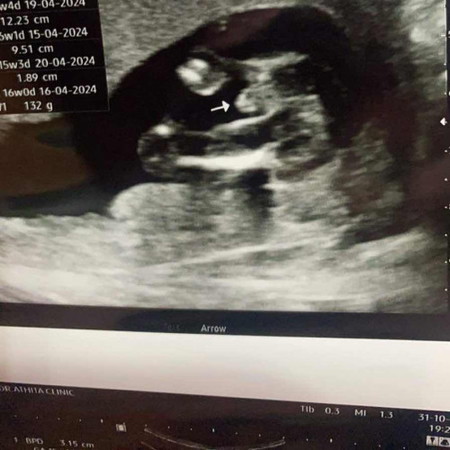

แม่ๆช่วยดูหน่อยค่ะว่าได้ลูกชายจริงไหมส่วนตัวแม่อยากได้ลูกชายมากๆ#ท้องแรกคะ ในรูป16wค่ะ

ผู้ชายจ้า อ้าขาโชว์ขนาดนั้น😀

ผู้ชายค่ะเห็นจู๋ออกขนาดนั้น

ยินดีด้วยนะคะ ได้ชายค่ะ

ชายค่ะ ☺️

ชายค่ะ